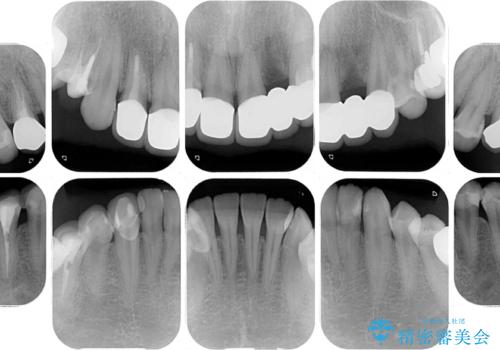

以前の治療箇所が痛む 全顎的なむし歯治療

また、奥歯にも痛みがあったり治療途中で放置されていたりと、全顎的な治療が必要な状況でした。

その後、奥歯は痛みのある部分から少しずつ、根管治療やインプラント治療などを行うこととしました。

インプラントが必要となった奥歯は、インプラントが埋入できないほど隣の歯の根尖病変が非常に大きかったため、根管治療を行ったうえで半年ほど待ち、骨が再生したことを確認してからインプラントを埋入しました。期間は長くかかりましたが、大変良い仕上がりとなりました。